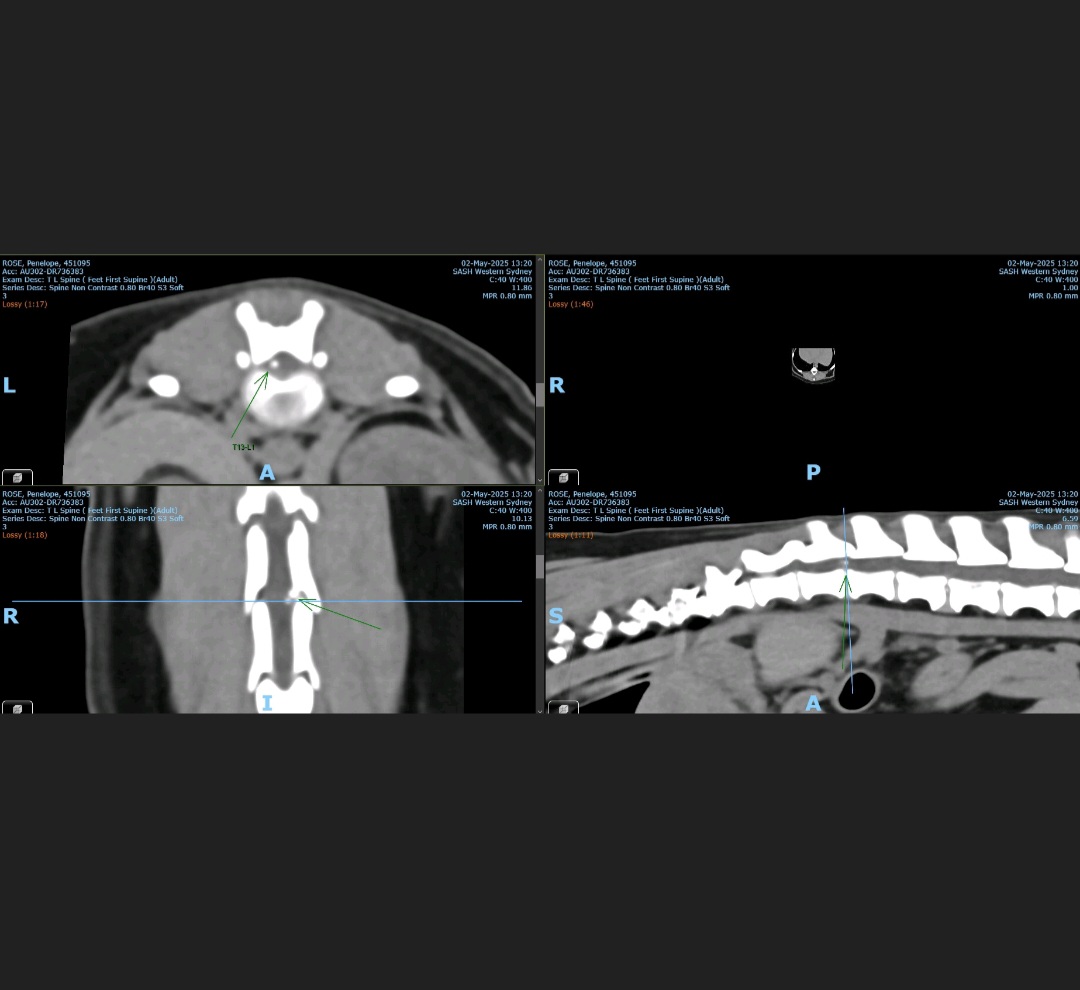

Miss Penelope Rumi Rose (she was going to be called Rumi but Beyoncé stole it) is a miniature long hair dachshund. She is 7 years young and full of love and spirit. Unfortunately though, like many other dachshunds she has lost control of her hind legs. There were no warning signs, no gradual decline, no prepartion, she just lost control. The vet is thinking IVDD, but also mentioned the big C, FCE and 3 other acronyms i can't remember.

We got medical attention as soon as possible, took her to 3 different vets all over western Sydney and finally found one that specialises in small animals, SASH. But like any specialist for humans, it came with massive price tag. I was quoted $14000 to $18000 for treatment, this includes possible spinal surgery, vet stays, medications, anaesthesia, assessments and most likely physio.